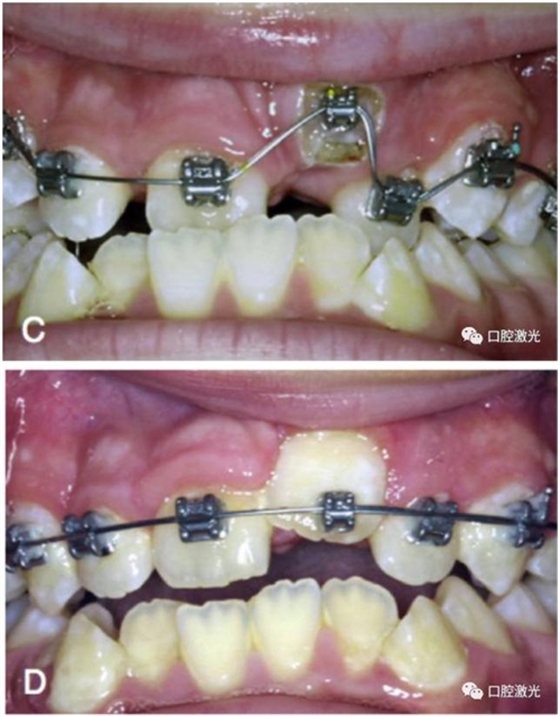

智齒盲袋切除

許多患者由于智齒盲袋的存在妨礙了正畸治療的進行。通過口腔激光進行盲袋切除后,立即可以繼續(xù)正畸治療。需要注意的是,激光盲袋切除是為數(shù)不多幾個僅僅采取表麻可能不能滿足,而需要注射局部麻醉的手術(shù)。

A盲袋覆蓋了第二磨牙的中遠端

B激光盲袋切除后立即實施正畸治療